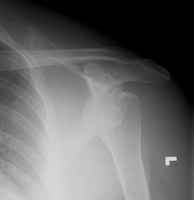

- Click on the image for a larger versionCGrashey radiograph of the left shoulder. This shows the fractured portion of the coracoid process as well as the anterior dislocation of the humeral head.